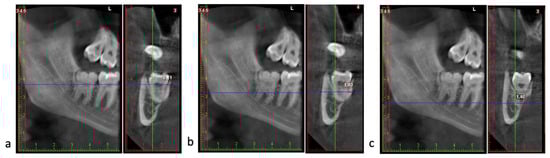

Prevalence and Radiographic Patterns of Impacted Third Molars in a Portuguese Population: A Retrospective Orthopantomography (OPG) and Cone-Beam Computed Tomography (CBCT) Study

by Ana Catarina Pinto, Helena Francisco, Maria Inês Charro, Duarte Marques, Jorge N. R. Martins and João Caramês

Background/Objectives: Impacted third molars are frequent and may increase surgical complexity, particularly when the mandibular third molar is in close proximity to the inferior alveolar canal (IAC). This study aimed to estimate the prevalence and impaction patterns of third molars in a Portuguese [...] Read more.

Background/Objectives: Impacted third molars are frequent and may increase surgical complexity, particularly when the mandibular third molar is in close proximity to the inferior alveolar canal (IAC). This study aimed to estimate the prevalence and impaction patterns of third molars in a Portuguese population and to characterize, using a nested CBCT subsample, the three-dimensional relationship between mandibular third molars and the IAC, including cortical integrity and lingual plate thickness. Methods: A retrospective observational analysis of 1062 orthopantomograms (OPGs) was performed to determine the prevalence and panoramic patterns using Winter, Pell and Gregory classifications and Rood–Shehab signs. A consecutive CBCT subsample (n = 205) was assessed for IAC position, contact status (no contact; contact with cortical bone; contact without cortical bone), cortical integrity, and lingual plate thickness. Descriptive statistics were complemented by effect sizes to support clinical interpretability. Results: The prevalence of impacted third molars was 34.9%, occurring predominantly in the mandible. Vertical angulation was the most prevalent pattern in both jaws. In the CBCT subsample, IAC position and contact patterns varied widely, and loss of cortical integrity was more often observed when panoramic high-risk signs were present. No clinically meaningful left–right asymmetry was identified across key anatomical risk indicators. Conclusions: In this Portuguese cohort, impacted third molars showed consistent panoramic patterns, while CBCT provided clinically relevant three-dimensional risk descriptors—particularly IAC contact type and cortical integrity—supporting selective CBCT use based on anatomical risk indicators rather than routine imaging. Full article